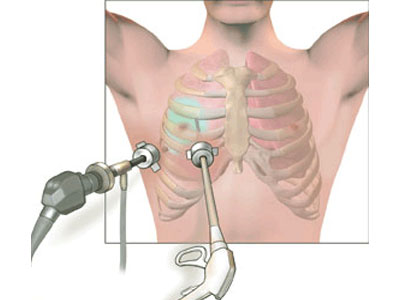

A Thoracotomy is a surgical procedure to gain access into the pleural space of the chest.[1] It is performed by surgeons (or emergency physicians under...